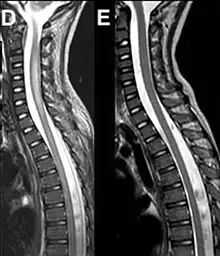

Magnetic resonance imaging of the spinal cord in a case of AFM showing cord swelling in (d) which has resolved three weeks later in (e).[2] | |